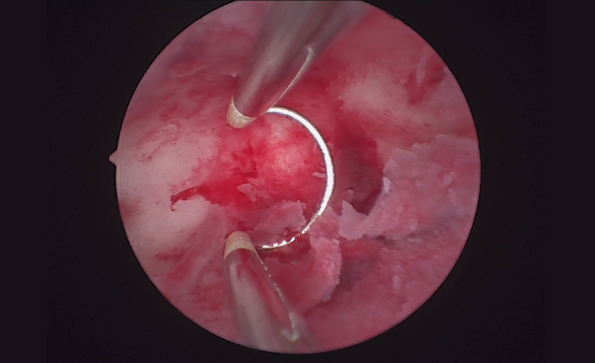

宮腔鏡系統包括哪些設備?如何消毒?